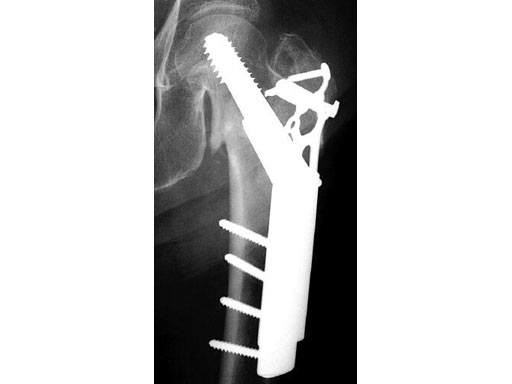

The Locking Trochanter Stabilization Plate is intended for the treatment of unstable pertrochanteric fractures in combination with the Dynamic Hip Screw (DHS), especially for 4-part fractures with greater trochanter.

Using the plate limits the possibility of varus deformation of the proximal fragment by cutting out the screws and medialization of the distal femoral fragment, without impairing the function and dynamization capacity of the DHS. The Locking Trochanter Stabilization Plate limits diaphyseal medialization by fastening onto the greater trochanter relief. The additional proximal internal fixaton can be achieved by using 3.5 mm locking head screws.

79-year-old woman.